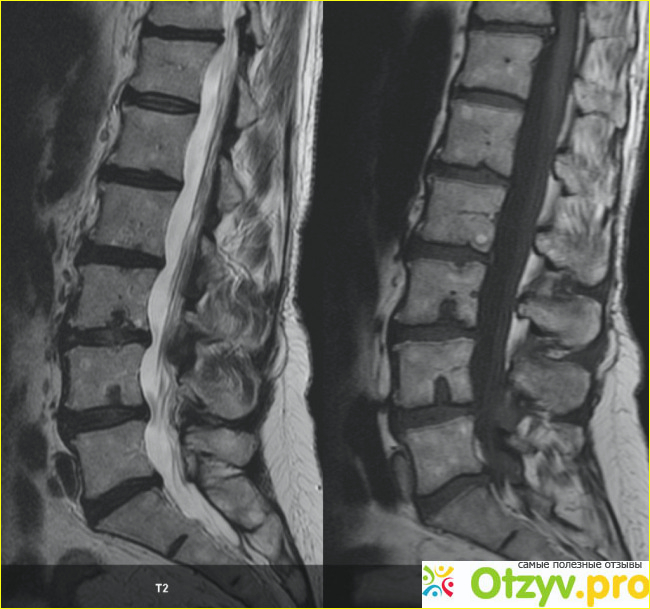

Чтобы правильно диагностировать заболевание, вам необходимо провести серию исследований. Чтобы диагностировать ретролистез и количественно оценить его степень, необходимо сделать рентген, магнитно-резонансная томография, электронейромиография. Если вы подозреваете, что начинается компрессия нерва, может быть целесообразно использовать нейрофизиологические тесты.